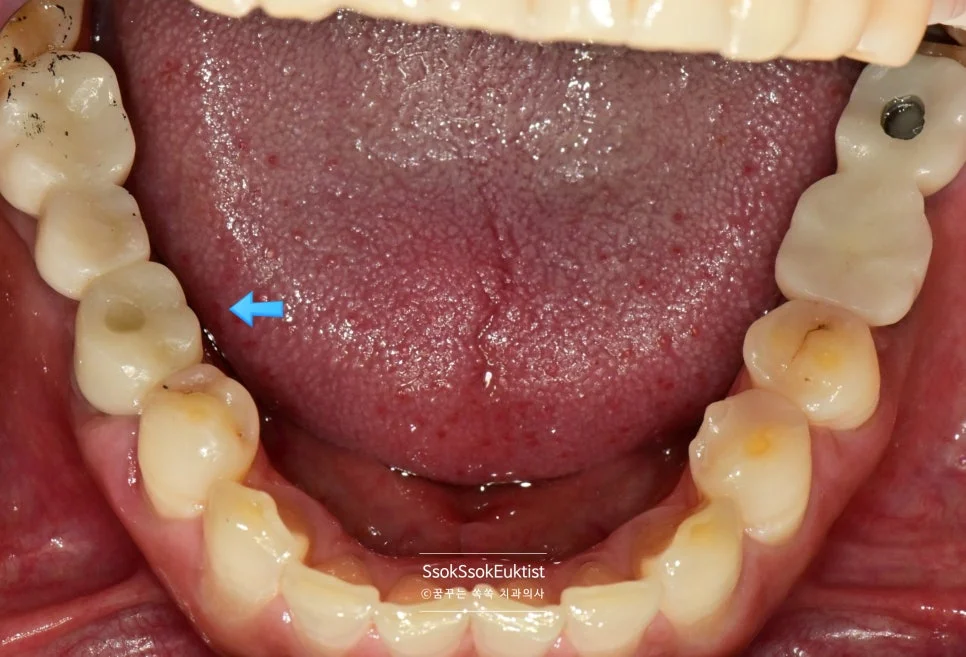

임플란트 식립한 자리 주변이 예쁘게 잇몸으로 아문 것을 볼 수 있습니다.

이제 묻혀 있는 임플란트를 꺼내어 보철물을 연결하면 치료는 마무리됩니다.

2번 자리의 잇몸을 보면 처음보다는 훨씬 건강한 잇몸이 된 것을 볼 수 있는데요. 한 달 후 체크 약속에서도

1개월 후 경과 관찰 — 2번 자리 잇몸이 건강하게 자리 잡아가는 모습

건강한 잇몸이 자리 잡아가는 것을 볼 수 있습니다.